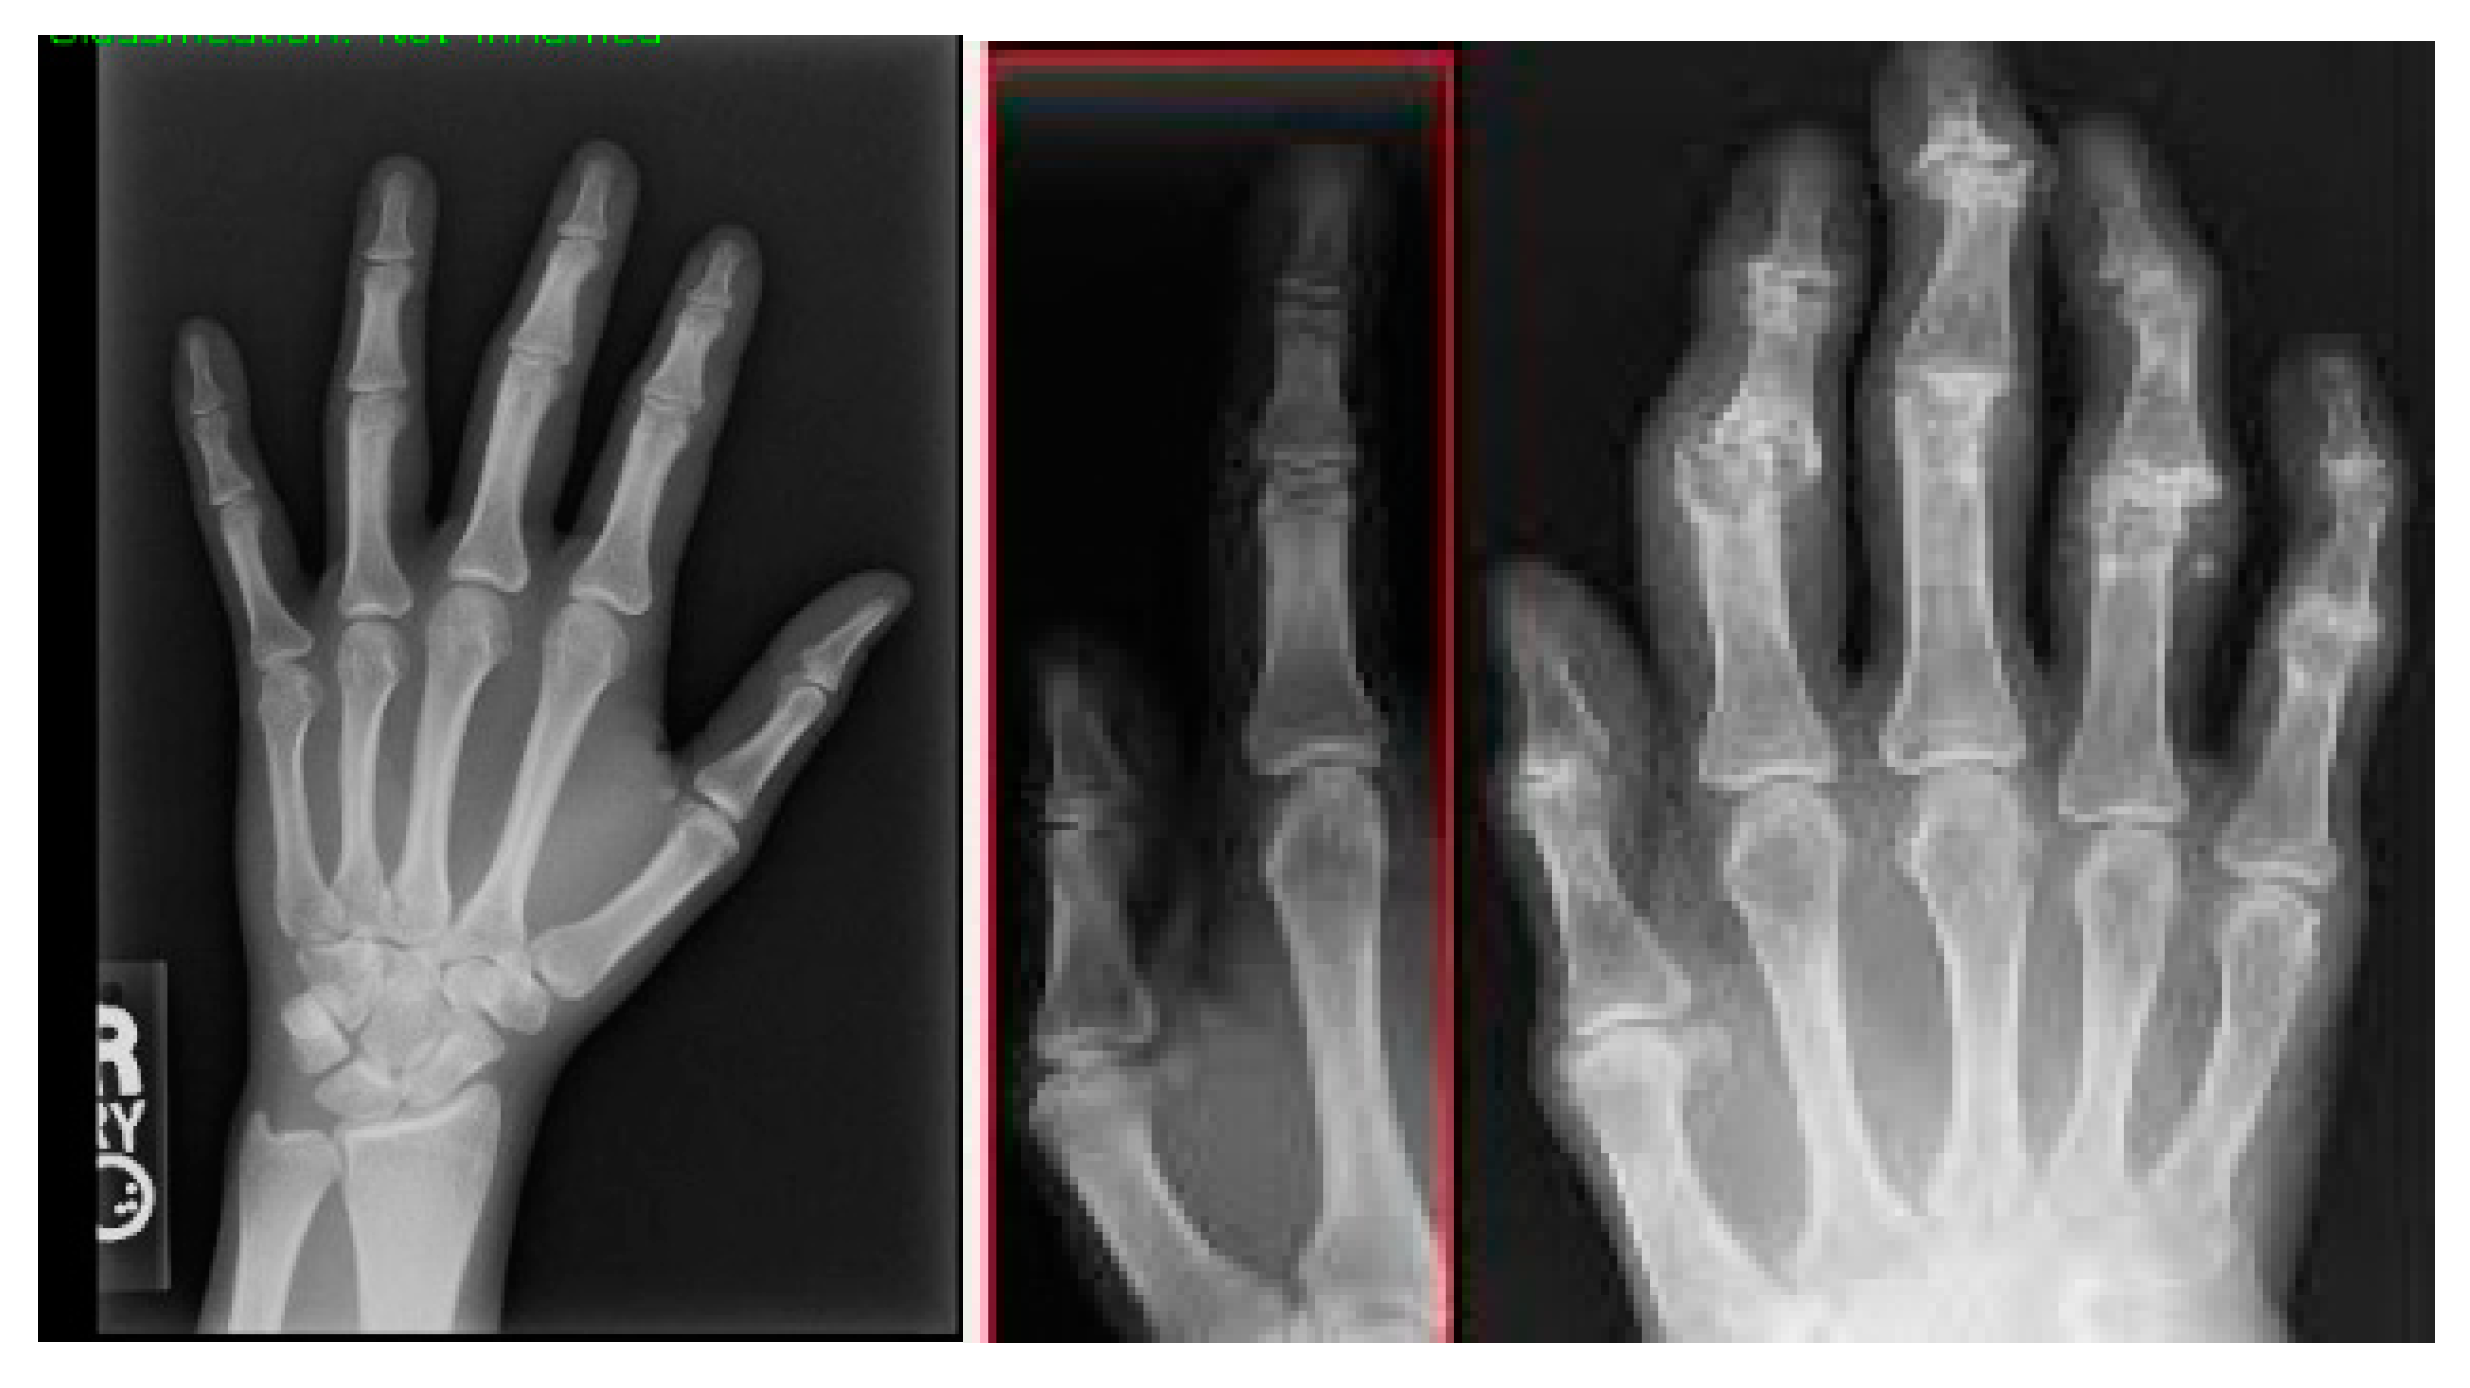

Figure 3 shows the segmentation of carpal bones of the wrist by hand X-ray images. The original hand image with its original black structure is the input; then, the application of global thresholding followed to constitute a binary mask. This thresholding technique demonstrated the capability of distinguishing the bone tissue from the background. Then, after all the bones had been segmented, contours were drawn that indicate the borders of the carpal bones. This visual representation enables the doctor to have a better understanding of the internal structures of the wrist.

Figure 3. A sample of images after segmentation of carpal bones.